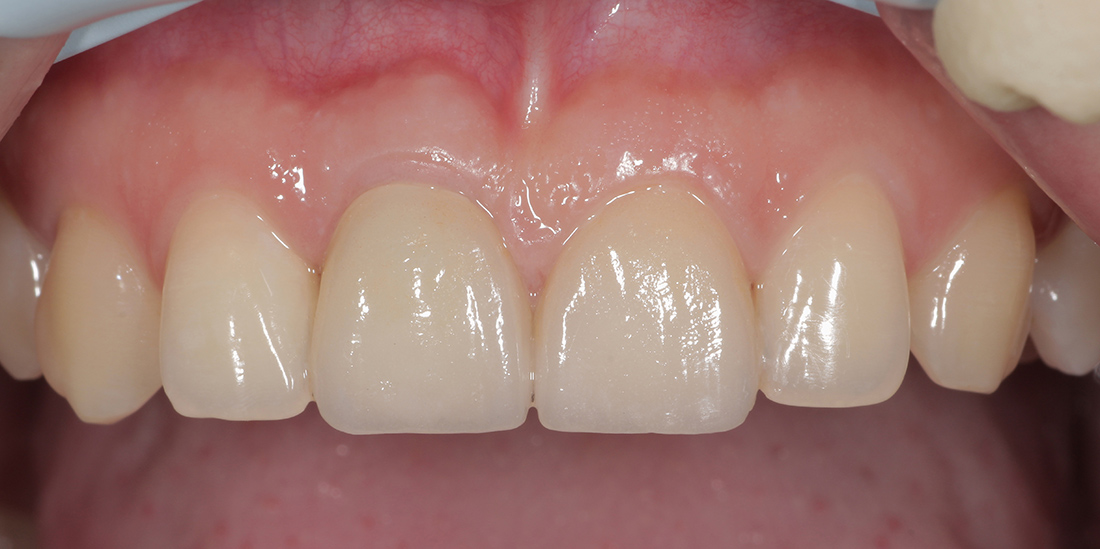

Под местной анестезией был удален зуб, установлен имплант, проведена пластика мягких тканей и фиксирована временная коронка. Через три месяца проведена оценка импланта, и мы перешли к замене временной коронки на постоянную. Опорой для коронки на импланте послужил индивидуальный циркониевый абатмен.

Для закрытия диастемы- промежутка между центральными зубами, было решено дополнительно изготовить винир на соседний зуб. Коронка и винир были изготовлены из цельнокерамического материала E.Max Press, позволяющего создать наиболее естественные и эстетические реставрации. Фиксация ортопедических конструкций была проведена за один этап.

Финальным результатом лечения остались довольны и пациентка, и мы.